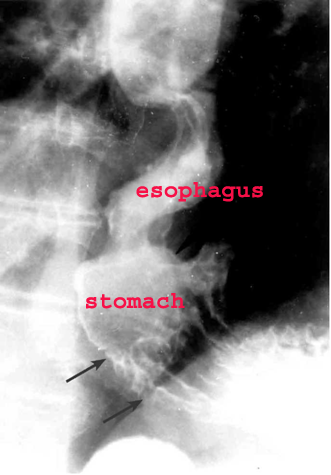

- בבליעת בריום אפשר להוכיח שאכן הצל הוא פונדוס הקיבה (תצלום 11.1)